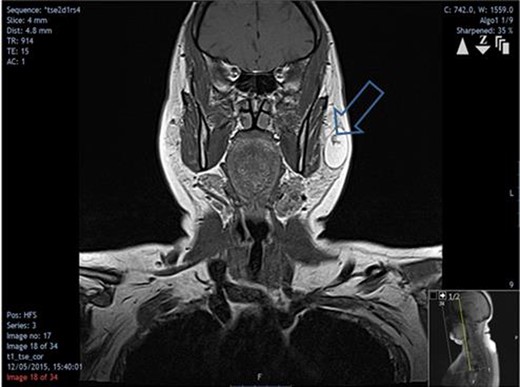

An US scan showed a well-defined non-vascular hypoechoic lesion in the left superficial parotid lobe measuring 3.2 × 2.2 × 2.6 cm (Fig. 2). The corresponding fine needle aspirate cytology was inconclusive. MRI showed high signal intensity on T1-weighted images (Fig. 3) and a branching vessel-like central structure traversing the lesion. These results were consistent with a lipomatous lesion. Surgical removal was performed via an extra-capsular dissection with facial nerve preservation. The tumour comprised of a well-circumscribed, soft yellow, fatty mass covered in a thin fibrous capsule (Fig. 4). Postoperative facial nerve function was normal with transient altered sensation to the ear lobe. Histopathology showed a homogenous proliferation of mature adipocytes, confirming the diagnosis of a lipoma. On 6-month review, there are no signs of recurrence.

Coronal MRI showing the extent of the lipoma and vessel-like structure traversing it (arrow).